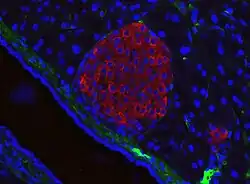

A pancreatic islet from a mouse in a typical position, close to a blood vessel; insulin in red, nuclei in blue. | |

A large amount of blood flows through the islets, 5–6 mL/min per 1 g of islet. It is up to 15 times more than in exocrine tissue of the pancreas.[10]